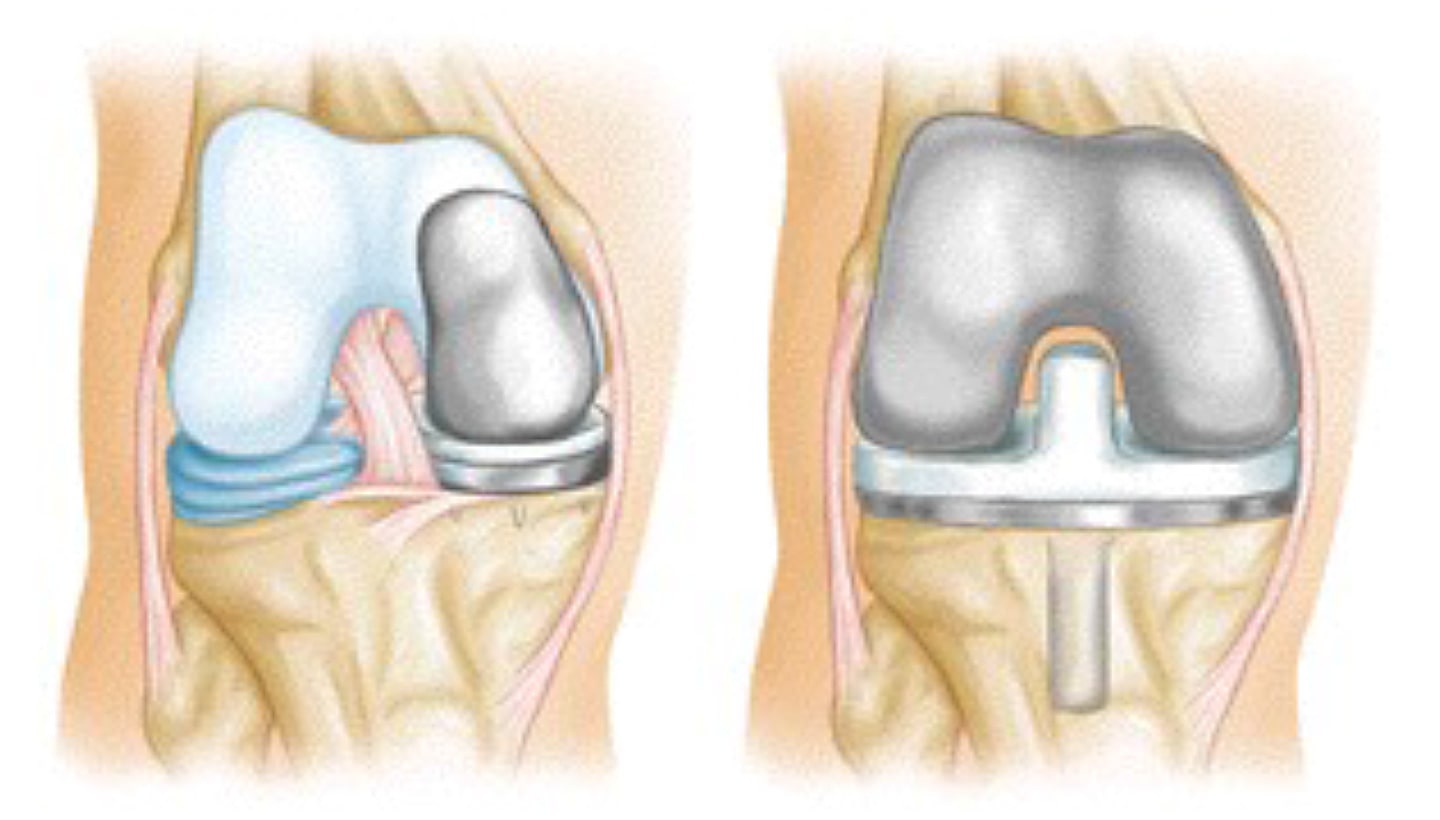

Total eller delvis kneutskifting (artroplastisk). Legen din vil fjerne skadet brusk og bein, og deretter plassere nye metall- eller plastflater for å gjenopprette knefunksjonen.